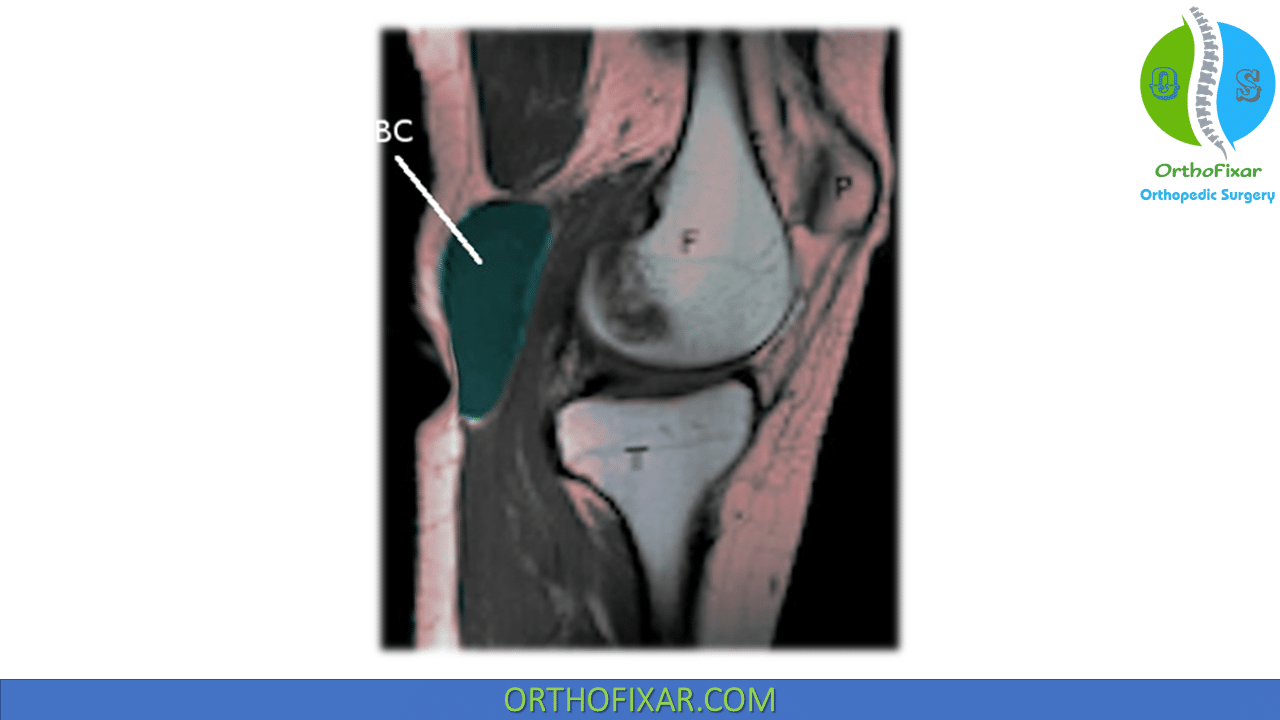

From orthofixar.com

Baker's Cyst Aspiration OrthoFixar 2024 Baker's Cyst Knee Aspiration baker cysts develop when something damages your knee joint or the tissues around it and extra fluid drains out of your. baker’s cysts, also known as popliteal cysts, form a lump at the back of the knee that can cause stiffness and discomfort. They typically result from a problem inside the knee joint, such as osteoarthritis or a. Baker's Cyst Knee Aspiration.